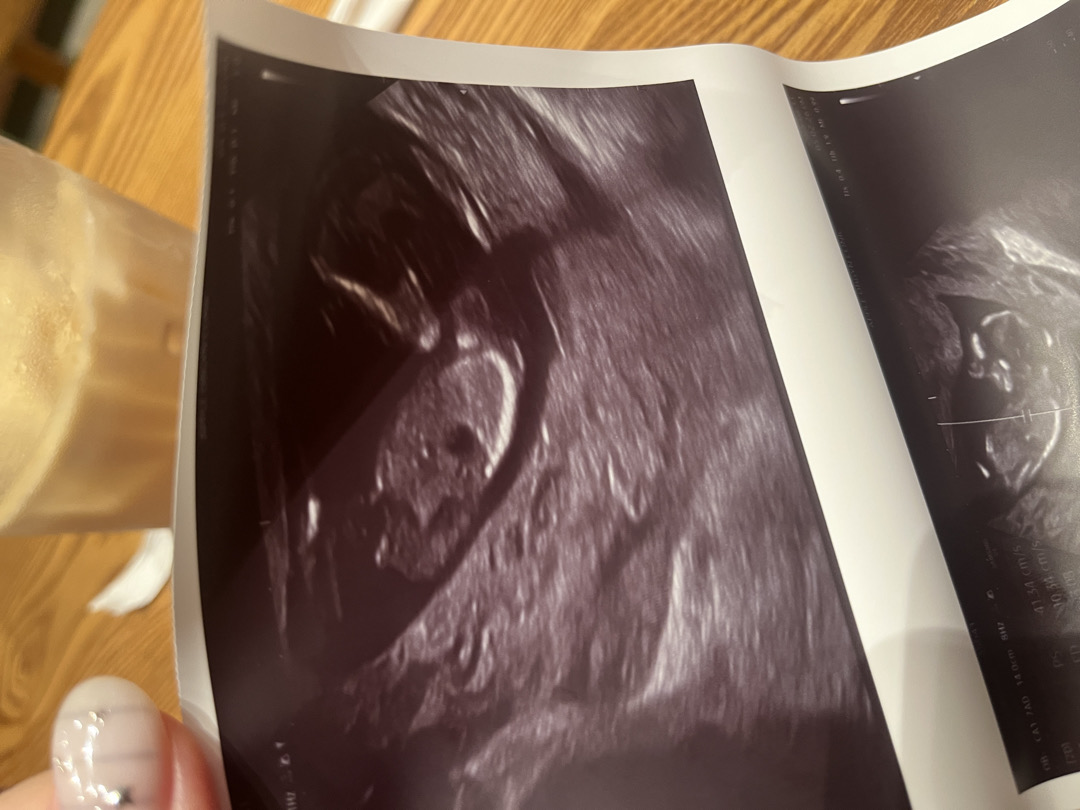

13주 성별질문 드려요!!!

서브병원에서 오늘 초음파 못본다해서 다른병원 (처음가봤어요!)갔더니 영상은 안주시네요 ㅜㅠㅠ 사진만 받아왔는데 이걸로도 알 수 있을까요? 입덧약 받으면서 겸사겸사 성별 궁금해서 간건데 뭐가 보이는거같긴한데 소음순이 크게보이는걸수있다며 아들같긴한데 하시며 아직 잘모르겠다고 하시더라구요 ㅜㅠ 화질도 좋지 못해서 죄송하네여 ㅠㅠ

13주차 사진도 딸로보이시나요? ㅎㅎ 후 넘 궁금해요 ㅠ 몇주뒤면 그래도 확실히 알텐데 시간이 안가네요 ㅋㅋ 이럴거면 성별때문이라도 니프티할걸 그랬어요

이건 11주때 초음파사진 각도법으로 딸같긴 했는데 ...ㅎㅎ..